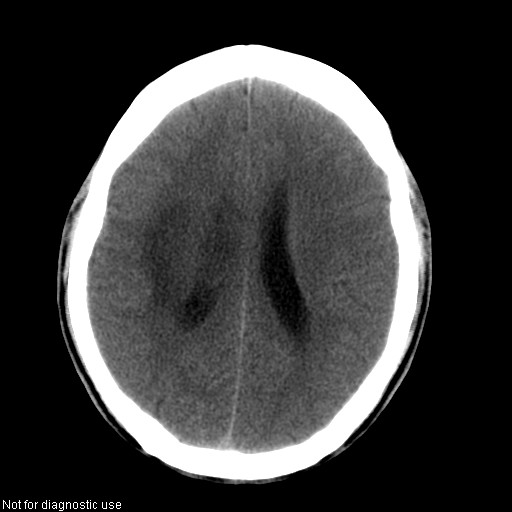

以下是引用hhcckk在2008-1-26 16:03:00的发言:[br]考虑病毒感染可能性大[br]1、病人发病时间短,1周,转移病灶时间长[br]2、楼主虽然没有告诉我们年龄,但从颅内情况来看,病人年纪不会很大,脑池,脑沟不是很明显,当然,可能有脑肿胀的原因,转移灶病人年纪一般较大[br]3、从病灶特点来看,转移多发生在灰白质交界区,多有指状水肿,占位效应明显,此病人呈对称性发布,发生在脑实质深部,与转移有所区别[br]4、病人经抗炎,止咳效果不好,可能是病毒感染,抗生素治疗效果不好[br]5、建议楼主1、增强 2、有呼吸系统的症状何不拍个胸片